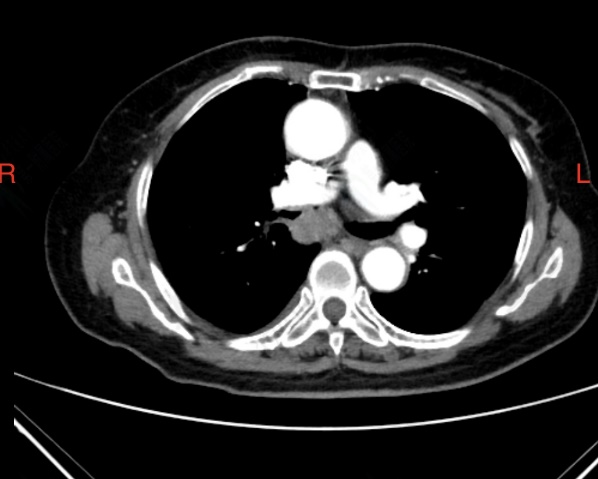

夏奶奶近两年来一直被间断的胸闷、气短、咳嗽、咳痰困扰。半月前,她的病情急剧加重,出现了痰中带血的症状,家人紧急送至东院区。呼吸与危重症医学科阎杰副主任医师接诊后,立即为夏奶奶进行胸部增强CT检查。结果提示“右肺门增大,右肺主支气管内结节状软组织密度灶,右肺下叶不张”,高度怀疑恶性肿瘤。

患者CT检查